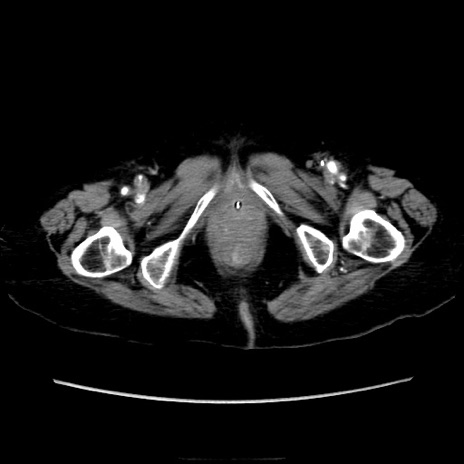

症例40(横断像)

横断像